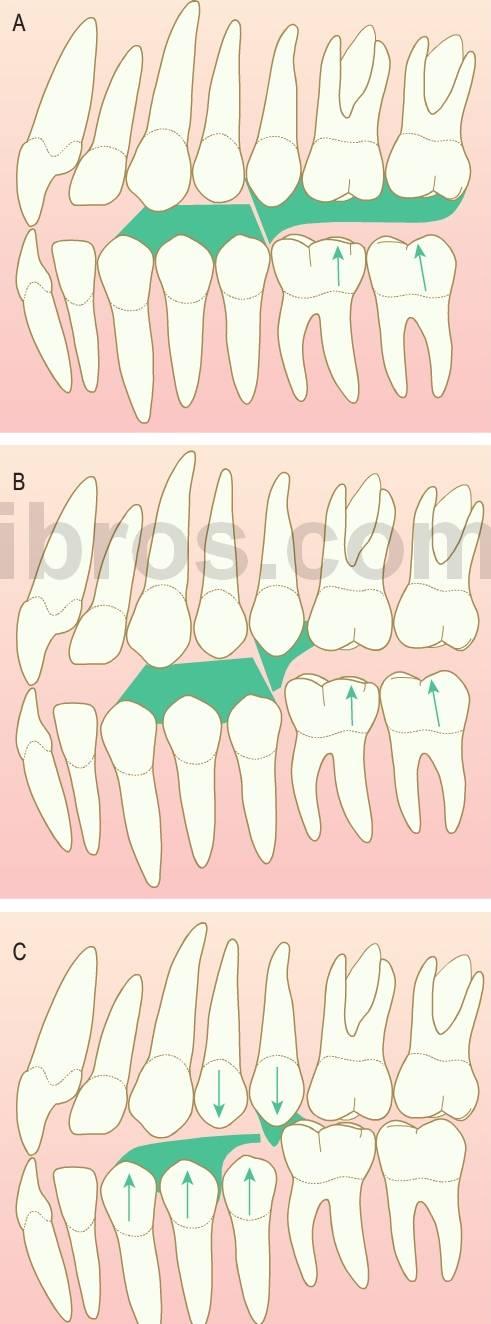

Siempre que se produzca la pérdida prematura de un segundo molar temporal, antes o después de la erupción del primer molar permanente, se producirá alguna pérdida de longitud de arcada provocada por el desplazamiento mesial del molar permanente (fig. 11.3).

Recuperación de espacio

Dentro de una arcada se puede necesitar la recuperación de espacio cuando ya se ha producido la migración de los dientes permanentes tras la pérdida de los dientes deciduos adyacentes. En ese momento, también se necesitaría el mantenimiento de espacio hasta la erupción del sucesor permanente. En el maxilar se interceptaría una relación dental de clase II en desarrollo, secundaria a la migración mesial y a la rotación del primer molar y, finalmente, en la mandíbula podría impedirse una ligera relación dental de clase III mediante el enderezamiento de los molares inferiores inclinados. La corrección dental no tendría ningún efecto en el problema esquelético subyacente en aquellos individuos con una discrepancia esquelética en desarrollo (fig 11.5).